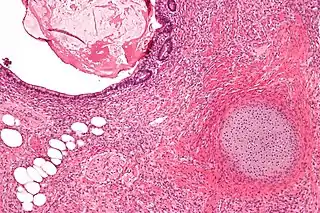

![]() Micrografía de un teratoma con componentes gastrointestinales (arriba a la derecha) cartílago (abajo, a la derecha) y tejido adiposo (abajo a la izquierda). Tinción con hematoxilina-Eosina. | ||

Es fácil identificar las tres capas que la conforman. Los tejidos del teratoma pueden ser muy similares a los tejidos que los rodean. Se ha informado de teratomas que contienen pelo, dientes, hueso, y muy raramente órganos más complejos como el corazón,[1][2] torso,[3][4] manos, pies, y otros miembros.[5] Normalmente, un teratoma no contendrá órganos, sino uno o más tejidos que normalmente se encuentran en el cerebro, la tiroides, el hígado y los pulmones.

A veces el teratoma contiene en su cápsula uno o más quistes llenos de fluido y cuando se produce un quiste de gran tamaño el teratoma puede potencialmente producir una estructura que recuerda a un feto. Puesto que están encapsulados, los teratomas son habitualmente benignos, aunque se conocen algunas formas de teratoma maligno. Un teratoma maduro es típicamente benigno y se encuentra más habitualmente en mujeres, mientras que un teratoma inmaduro es típicamente maligno y se encuentra más a menudo en varones.